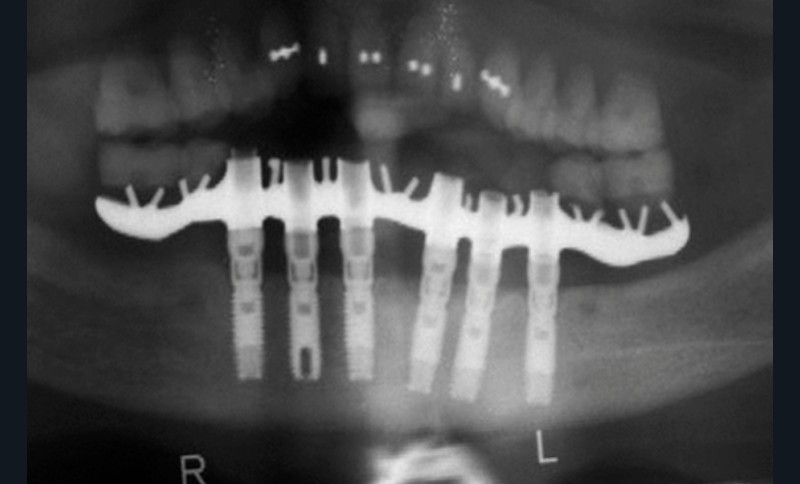

Voici quelques décennies que tout a commencé, par des réhabilitations complètes sur implants, uniquement sur l’arcade mandibulaire opposée à une prothèse amovible complète, avec le concept d’ostéointégration selon Brånemark (fig. 1) [1].

Les empreintes étaient réalisées à partir de connexions externes, les armatures étaient uniquement coulées en or ou en cobalt-chrome (fig. 2).

Le test de passivité de Jemt était obligatoire, les sections d’armatures fréquentes et la résine le seul matériau disponible. L’ostéointégration restait la seule priorité des praticiens. C’était l’implantologie chirurgicale.